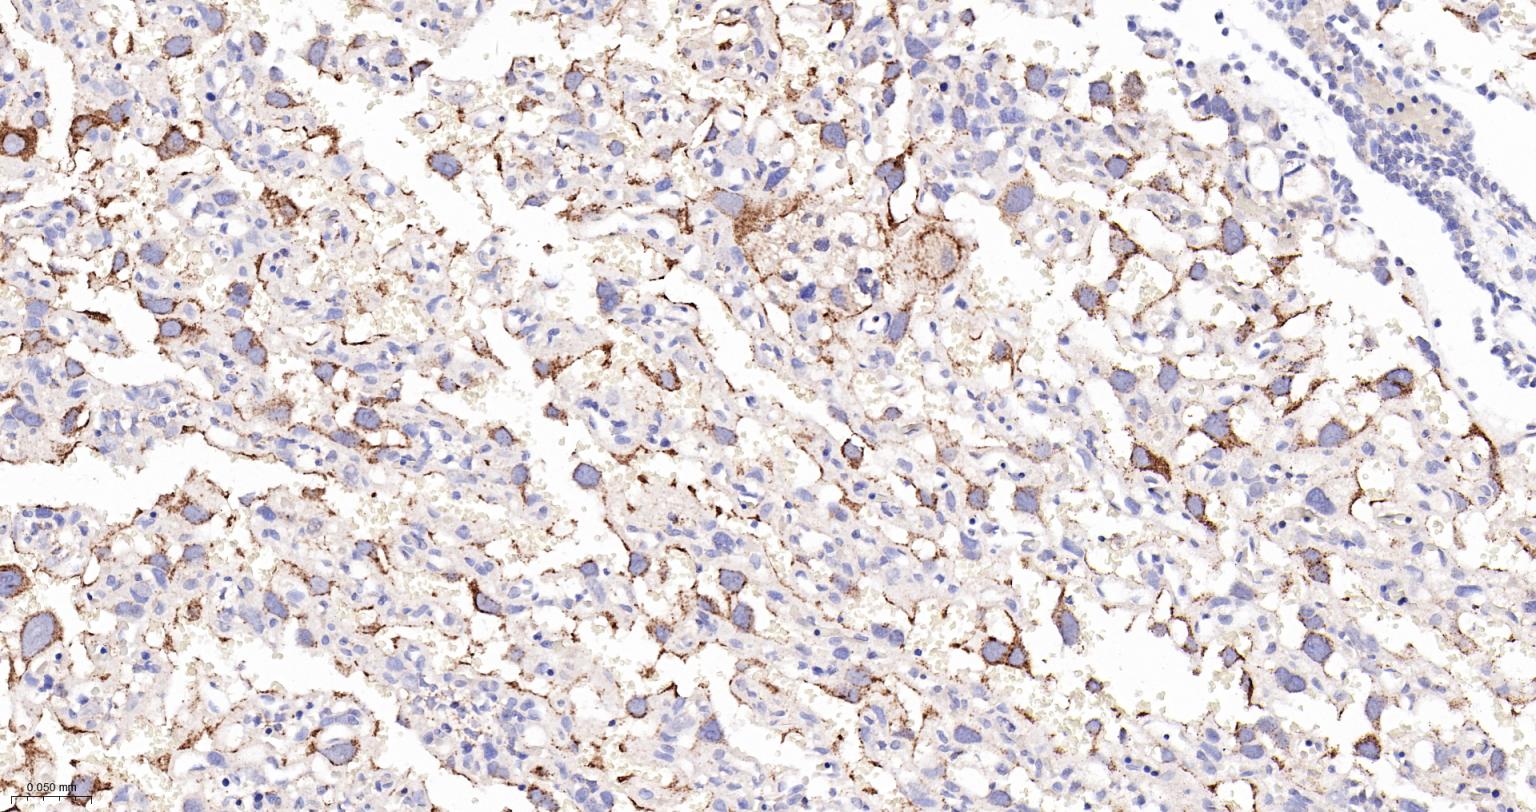

Paraformaldehyde-fixed, paraffin embedded Human liver cancer;Antigen retrieval by boiling in sodium citrate buffer (pH6.0) for 15 min; Antibody incubation with LAMP2 Monoclonal Antibody, Unconjugated (bsm-61207R) at 1:200 overnight at 4°C, followed by conjugation to the bs-0295G-HRP and DAB (C-0010) staining.